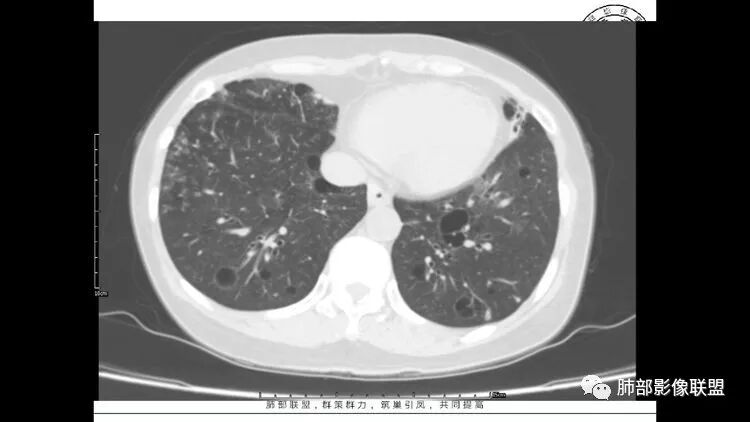

胸CT:1.双肺多发囊性变,以中下肺为主,病变边缘可见肺动脉,部分囊内可见分隔及肺动脉,双下部分肺野周围可见小叶中心结节及树丫征。

2 左肺上叶尖后段 右肺上叶前段 右肺下叶外基底段 结节影,边界清楚,可见柔软毛刺,左肺下叶后基底段混合密度影。

患者中年女性,因右眼红痛1天就诊。胸CT:双肺多发囊性变及结节影,囊以中下肺为多,部分囊内可见分隔及肺动脉,结节部分为实性,部分为混合性,边缘光滑,未见明显毛刺、棘突、胸膜牵拉及血管集束征象。双中下可见支气管扩张及树丫征。淋巴结无明显肿大。综合考虑:一元淋巴细胞间质性肺炎。多元鉴别肺腺癌并转移等恶性病变。

左肺下叶混杂密度病灶,其内可见空泡,周围ggo清楚,考虑浸润性腺癌。双肺散在多发薄壁囊腔和实性结节,以胸膜下及血管旁分布位于,气囊可见血管贴边征,双肺小叶间隔及中央间质增厚,局部可见磨玻璃影及树芽征,纵隔内淋巴结肿大,考虑LIP

综上,考虑左下肺浸润性腺癌+LIP

双肺下叶分布为主的间质改变(磨玻璃影、小叶间隔增厚)、散在气囊影(常有血管贴边)、边界不清小结节